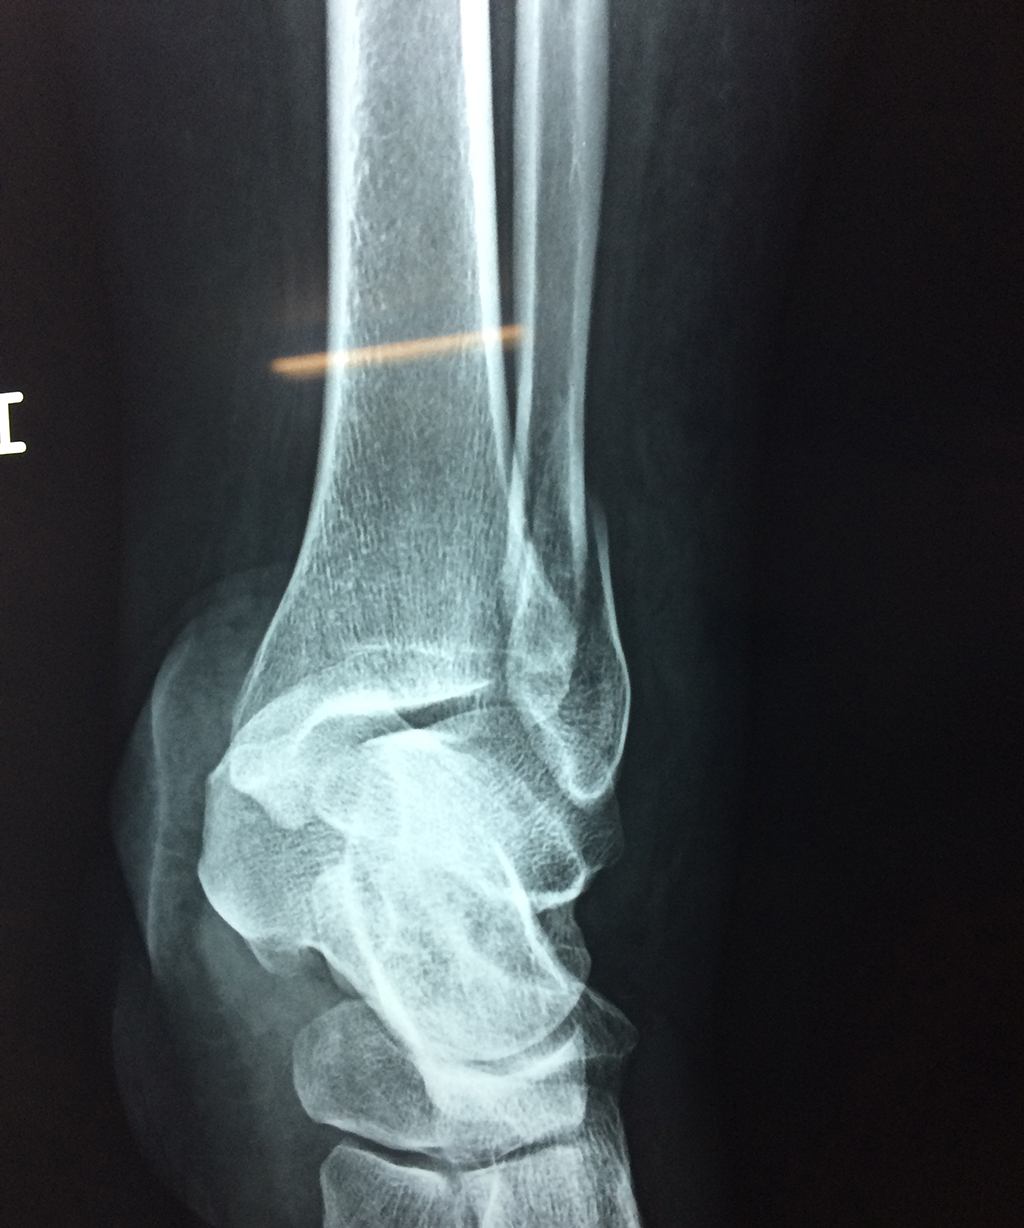

Una fractura de tobillo es la rotura de uno o más de los huesos del tobillo. Estas fracturas pueden ser:

Algunas fracturas de tobillo pueden requerir cirugía si:

- Los extremos de los huesos están desalineados entre sí (desplazados).

- La fractura se extiende hasta la articulación del tobillo (fractura intra-articular).

- Los tendones o ligamentos (tejidos que sujetan los músculos y los huesos entre sí) están rotos.

- El médico cree que sus huesos probablemente no sanen apropiadamente sin cirugía.